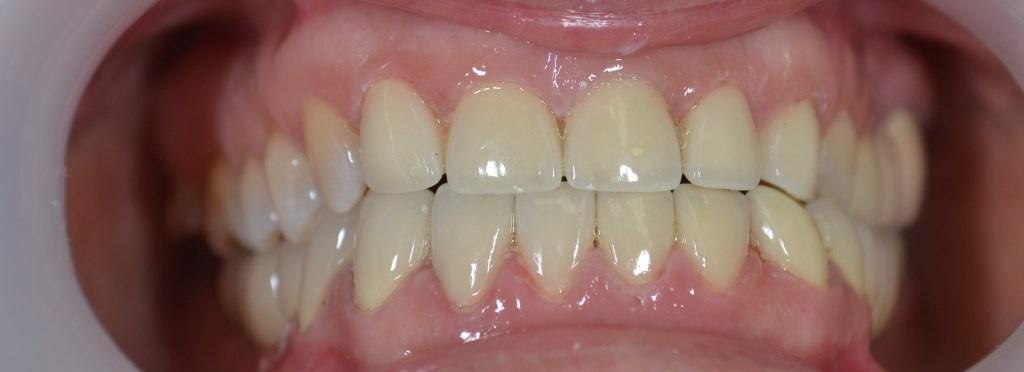

Kozmetikai kezelés: ínyvisszahúzódás és fognyaki kopások koronával történő korrekciója.

A választott korona típusa: CAD/CAM (komputer vezérelt tervezés/ megmunkálás) technológiával készült cirkónium (fémmentes) szóló koronák.

A választott fogszín: BL3 .

A protetikai munka elkészülésének ideje: 10 munkanap.